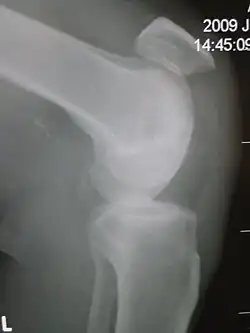

Patellar tendon rupture showing a marked distance between the tibial tuberosity and the bottom of the knee cap. | |

Patellar tendon rupture can usually be diagnosed by physical examination. The most common signs are: tenderness, the tendon's loss of tone, loss of ability to raise the straight leg and observation of the high-riding patella. Radiographically, patella alta can be detected using the Insall and Salvati method when the patella is shorter than its tendon. Partial tears may be visualized using MRI scans.[4]